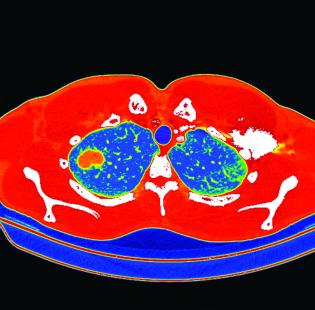

Alors qu’Emmanuel Macron a récemment entériné le principe d’un dépistage organisé du cancer du poumon en France, les résultats préliminaires de l’étude DEP KP80, présentés par le Dr Olivier Leleu (CH d’Abbeville) lors du Congrès de pneumologie de langue française, confortent en vie réelle l’efficacité et la faisabilité de la démarche. Cette étude lancée dans la Somme en 2018 visait à évaluer l’impact d’un dépistage basé sur la réalisation de trois scanners basse irradiation annuels, durant trois années consécutives, chez des individus âgés de 55 à 74 ans, avec un tabagisme de plus de 30 PA, actuel ou sevré depuis moins de 15 ans. Le troisième et dernier tour de scanner basse dose se terminera fin 2021.

Alors qu’Emmanuel Macron a récemment entériné le principe d’un dépistage organisé du cancer du poumon en France, les résultats préliminaires de l’étude DEP KP80, présentés par le Dr Olivier Leleu (CH d’Abbeville) lors du Congrès de pneumologie de langue française, confortent en vie réelle l’efficacité et la faisabilité de la démarche. Cette étude lancée dans la Somme en 2018 visait à évaluer l’impact d’un dépistage basé sur la réalisation de trois scanners basse irradiation annuels, durant trois années consécutives, chez des individus âgés de 55 à 74 ans, avec un tabagisme de plus de 30 PA, actuel ou sevré depuis moins de 15 ans. Le troisième et dernier tour de scanner basse dose se terminera fin 2021.

D’ores et déjà, les résultats des deux premiers rounds sont encourageants, avec un nombre important (75 %) de cancers découverts au stade localisé et un taux élevé de résection chirurgicale (87 %) seule ou associée à une radiochimiothérapie/chimiothérapie. « Le dépistage permet d’inverser les stades au diagnostic », se félicite Olivier Leleu, sachant que la survie à 10 ans dépasse 80 % pour les cancers découverts à des stades localisés par scanner thoracique basse irradiation. Seul bémol dans cette étude, le taux de participation (1 300 participants à l’inclusion) s’essouffle au second tour, atteignant à peine 35 %.

Deux publications de référence, l’essai néerlando-belge Nelson et l’étude américaine NLST (National Lung Screening Trial) avaient déjà montré l’intérêt d’un dépistage par scanner basse dose ciblé sur une population à risque de gros fumeurs. Avec, dans l’étude NLST, une diminution de la mortalité par cancer du poumon de 20 % et de la mortalité globale de 6,7 % et, dans l’étude Nelson, une mortalité spécifique réduite de 24 % chez les hommes et de 33 % chez les femmes.

Fort de ces résultats, l’Inca devrait lancer prochainement des expérimentations afin d’affiner les contours du dépistage à la française avant d’envisager probablement un programme national dans les prochaines années.

L’identification de phénotypes de patients BPCO progresse. Une étude rétrospective conduite par le CHU de Nancy a cherché à prédire, sur des critères d’imagerie, le phénotype « exacerbateur fréquent » (au moins deux exacerbations ou une hospitalisation au cours d’une année) chez 69 patients atteints de BPCO. Selon le Dr Mathilde Oranger, qui la coordonnait, « l’augmentation de la surface de la paroi bronchique de 3e génération permet de prédire le risque d’exacerbation dans l’année qui suit la réalisation du scanner thoracique ».